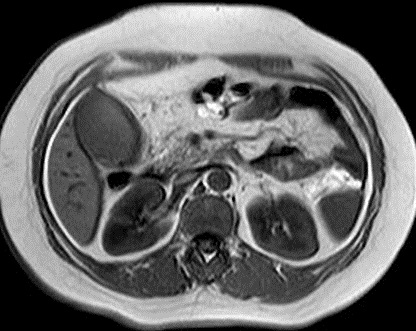

Image IRM : C'est image hypersignal de

vesicule biliaire dilate sur T2 avec grand calcul

hypointense a infundibulum . Image de compress du calcul sur

canal hepatique commune . Image de dilatation de voie

biliaitre hyperintense intrahepatique peut se en voyait sur

T2

Syndrome de Mirizzi : Image

distendue vesicule biliaire a isointense avec

epaississement de sa paroi : Image radiologique IRM

en coupe axiale pondere sur T1 |

Meme cas en coupe a

travers l'infundibulum de la vesicule biliaire : Une

grand calcul a hyposignal arrondie en coincee

a infudibulum de la vesicuile biliaire ( Image

radiologique IRM en coupe axiale sur T1 ) |